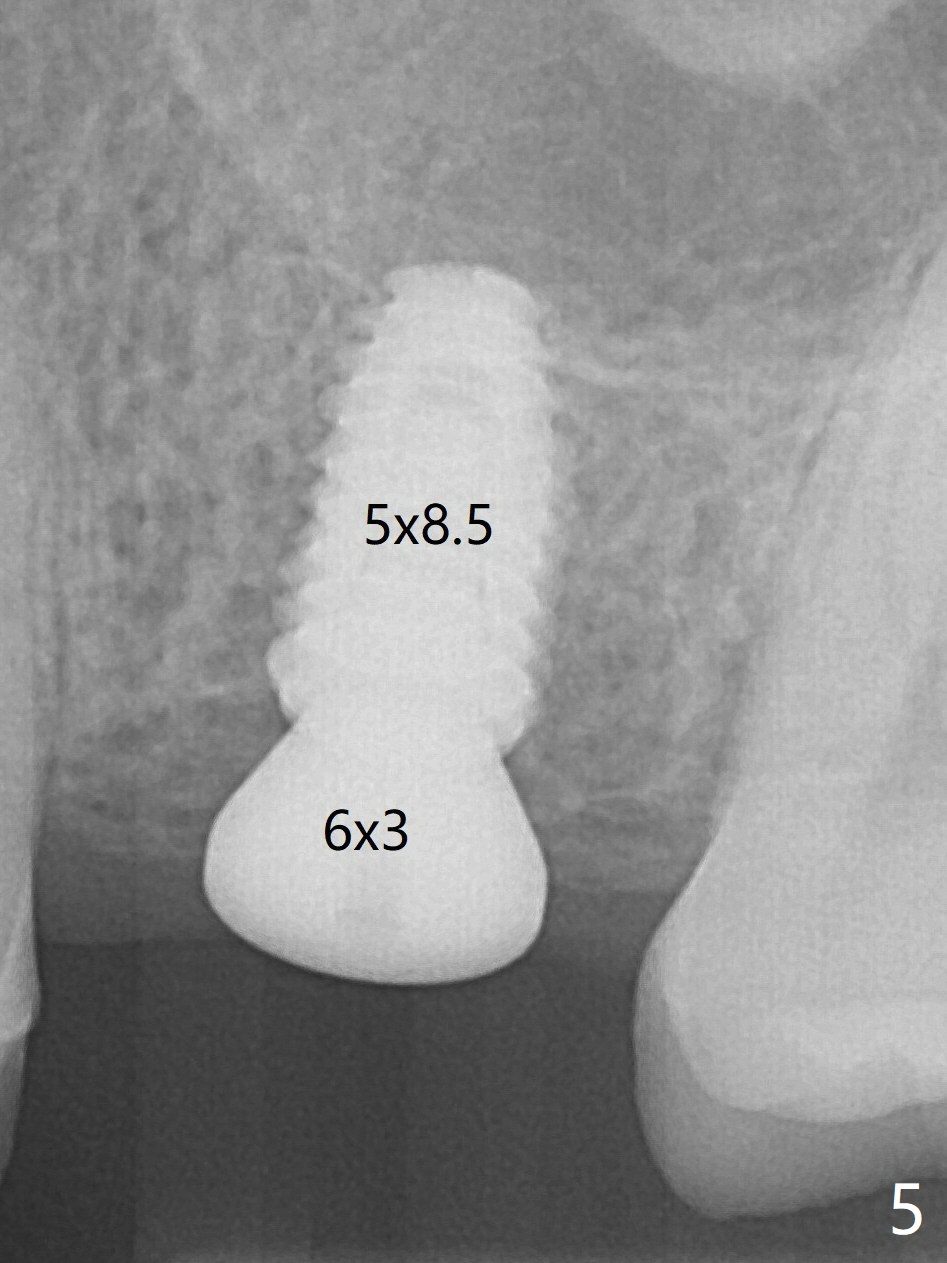

A 5x8.5 mm implant is placed with satisfactory insertion torque and depth, followed by insertion of a 6x3 mm healing abutment (Fig.5).  There is mild resorption of the sinus floor distally 3.5 months postop, although the implant remains stable (Fig.6).